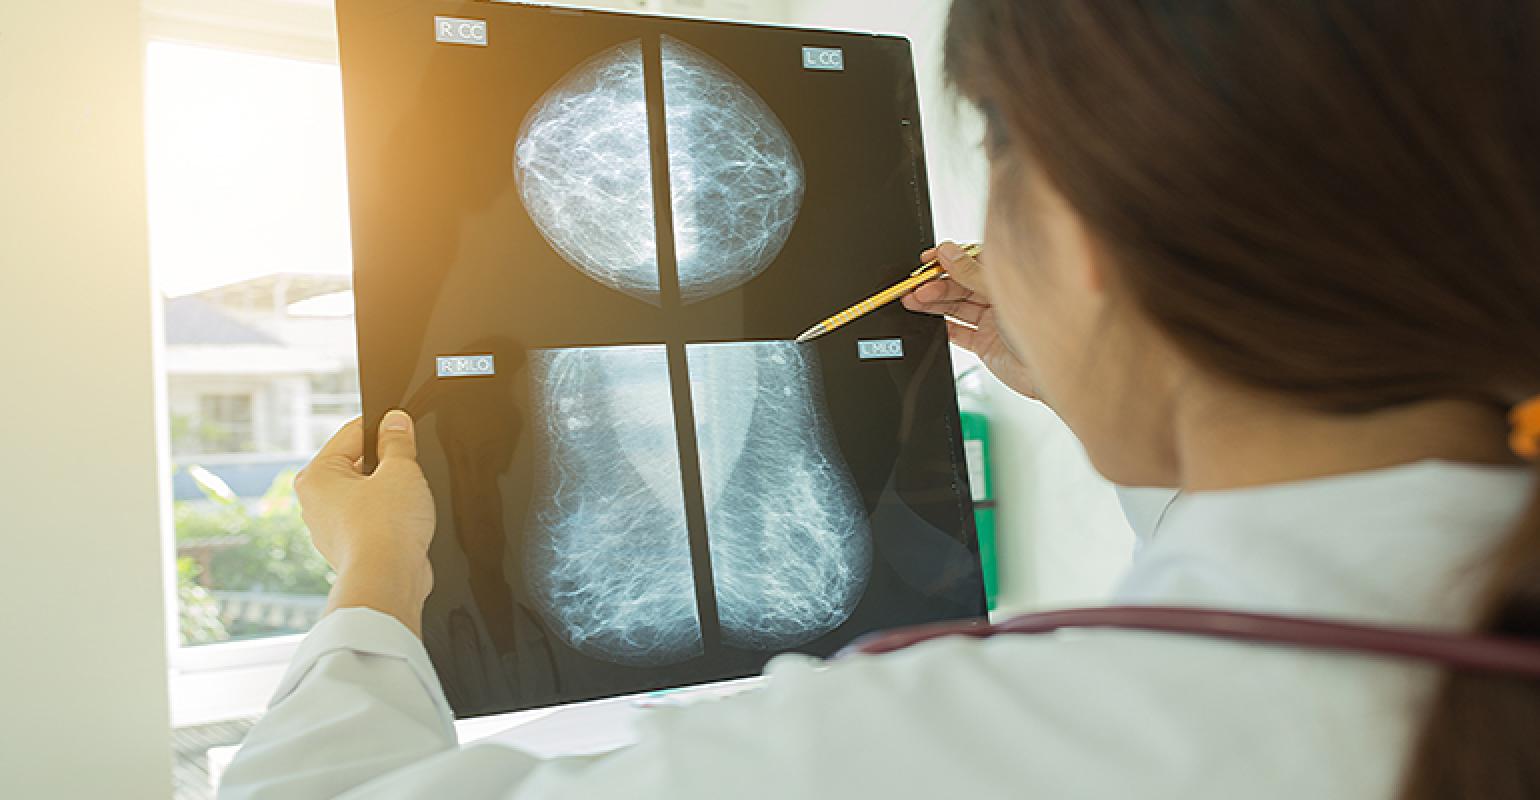

A mammogram is a low-dose x-ray of the breasts. Mammogram screening can detect breast cancer up to three years before a tumor can be felt during a breast exam. Without a cure for breast cancer, early detection is the very best defense.

When it comes to scheduling your mammogram, you will have the choice between 3D and 2D mammography. What’s the difference?